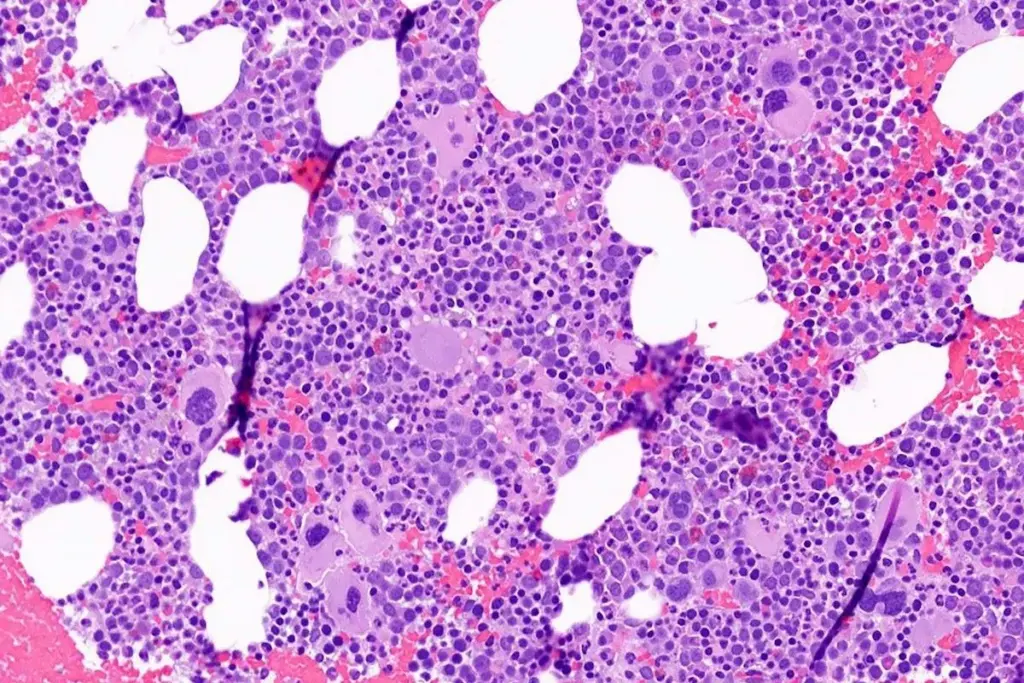

Bone Marrow Biopsy Procedures

A bone marrow biopsy is vital for diagnosing aplastic anemia. We take a sample from the hipbone. This test checks the bone marrow’s health.

We do bone marrow biopsies under local anesthesia to reduce pain. This test shows the bone marrow’s structure and cells, helping diagnose aplastic anemia.

To diagnose HAAA, doctors use clinical checks, lab tests, and bone marrow biopsies. The signs include low counts of blood cells and a small bone marrow.

Bone Marrow Biopsy |

Hypocellular marrow indicating bone marrow failure |